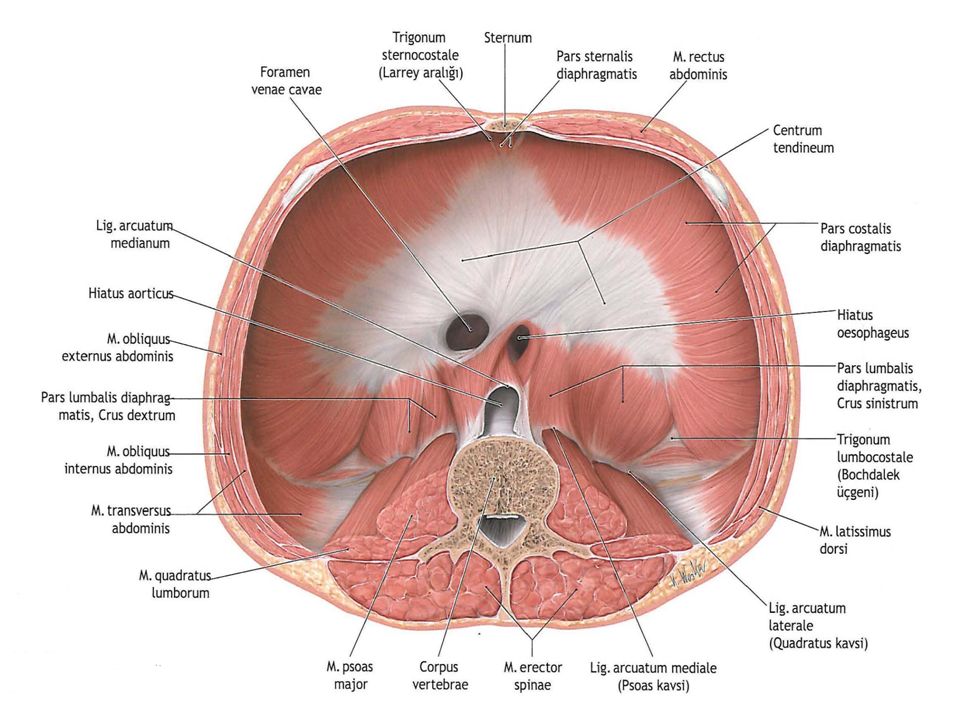

Анатомия диафрагмы и треугольника Бохдалека

Раздел: Визуальный дайджест